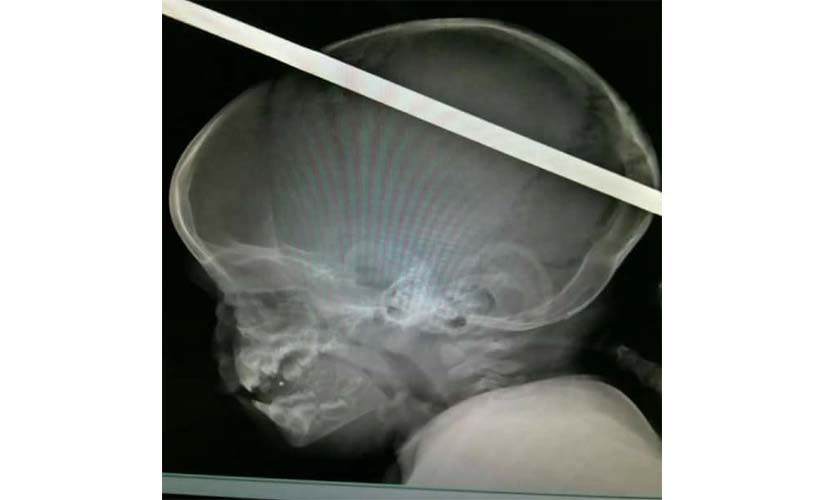

قام اللواء أحمد ضيف صقر بزيارة الطفل زياد بغرفه العناية المركزية بمستشفى الطوارئ للاطمئنان على حالته الصحية وكان الطفل زياد البالغ من العمر 11 شهرا قد نقل إلى مستشفى الطوارئ أثر اختلال توازنه وسقوطه على سيخ حديد طوله 40 سم اخترق رأسه حيث تم تشكيل فريق من الأطباء لجراحة المخ والأعصاب تكون من الدكاترة مصطفى شحاتة وعلى معارك وأحمد الشرقاوي وأحمد فتحي صلاح، وتم إجراء جراحة عاجلة له تمت بنجاح مذهل وصف بأنه معجزة في عالم الطب وقد اطمأن محافظ الغربية على صحة الطفل حيث أكد له الأطباء استقرار حالته الصحية وتماثله للشفاء هذا وقد صافح محافظ الغربية فريق الأطباء الذي أجرى الجراحة معربا لهم عن شكره وتقديره لما بذلوه من جهد في الجراحة التي استغرقت 6 ساعات لإنقاذ الطفل وليثبتوا للجميع قدرة الطبيب المصري على تحقيق المعجزات وليسطروا بأيديهم وبحروف من نور أسماءهم في عالم الطب وقد حث محافظ الغربية على تقديم كافه الرعاية الطبية للطفل.. كما قام محافظ الغربية بجولة داخل مستشفيات جامعة طنطا تفقد خلالها الأرض المزمع إقامة مستشفى الجراحات العامة الجديد عليها والبالغ مساحتها 3 آلاف متر والتي سوف توفر خدمه الجراحات اليومية المجاني للمواطنين.. رافق محافظ الغربية الدكتور أمجد عبد الرؤوف عميد كلية طب طنطا وعدد كبير من أطباء مستشفى الجامعة.

وقد أشاد الدكتور أمجد فرحات عميد كلية الطب بالفريق الطبي الذي حقق معجزة علمية غير مسبوقة تسجل له ولاسم كلية الطب وجميع الأساتذة والطلاب لهم أن يفخروا بهذه المعجزة العلمية التي تشرف الجامعة على مستوى مصر والشرق الأوسط

كما سيقوم الدكتور مجدي سبع رئيس جامعة طنطا بتكريم الفريق الطبي تقديرا لجهده العلمي ودوره الكبير في انقاد حياة الطفل زياد